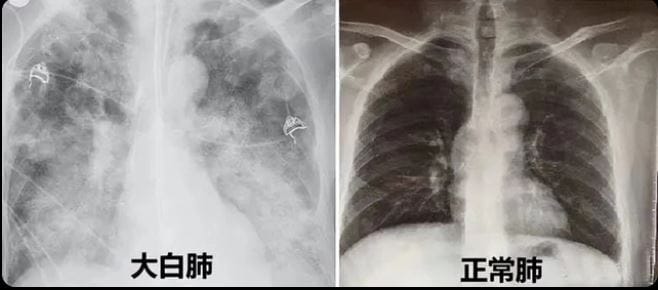

Finally, a major worry has been whether new, more severe variants might have popped up in China. There’s anecdotal evidence of patients in China suffering from breathing issues, with their CT scans showing lung inflammation.

- One explanation for such “white lungs” is that these individuals caught the original Wuhan strain - which caused lung inflammation - but didn’t do proper CT scans until now.

- Another explanation is that China’s Sinovac shots haven’t protected as well against Omicron as mRNA vaccines did in other countries.

- Lastly, some foreign governments worry that the white lungs are related to a new variant that could eventually spread to the rest of the world. The speed at which COVID-19 is spreading in China does suggest a variant with a higher reproduction rate than prior Omicron variants.

In any case, WHO met with Chinese officials in late December and has asked the National Health Commission to share sequencing data to ensure that it is indeed Omicron that spreading in China and not some newer, more problematic variant. The sequencing data retrieved so far suggests that there is no new variant.

I personally believe that the white lungs are from individuals previously infected with the original Wuhan strain. Nothing to be too worried about.